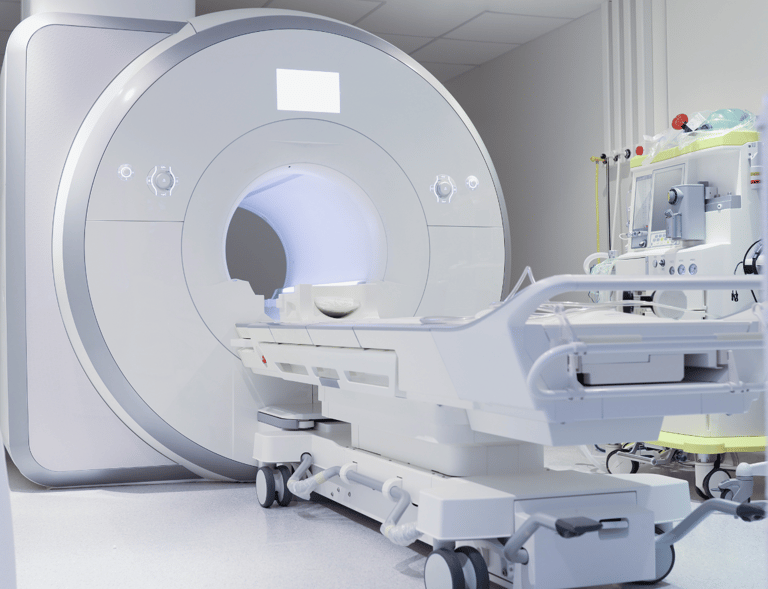

EQUIPOS DE IMANEOLOGÍA

Tecnología de última generación para diagnósticos precisos.

Mantenimiento y Soporte para Equipos Médicos

En LinkMedic nos comprometemos a mantener tus equipos médicos de radiología en su máximo nivel de rendimiento. Nuestro servicio técnico especializado asegura que cada equipo de imagenología opere de manera confiable y precisa, garantizando diagnósticos seguros y continuidad en la atención de tus pacientes.

Proveemos tecnología de última generación para clínicas y hospitales, garantizando diagnósticos precisos.